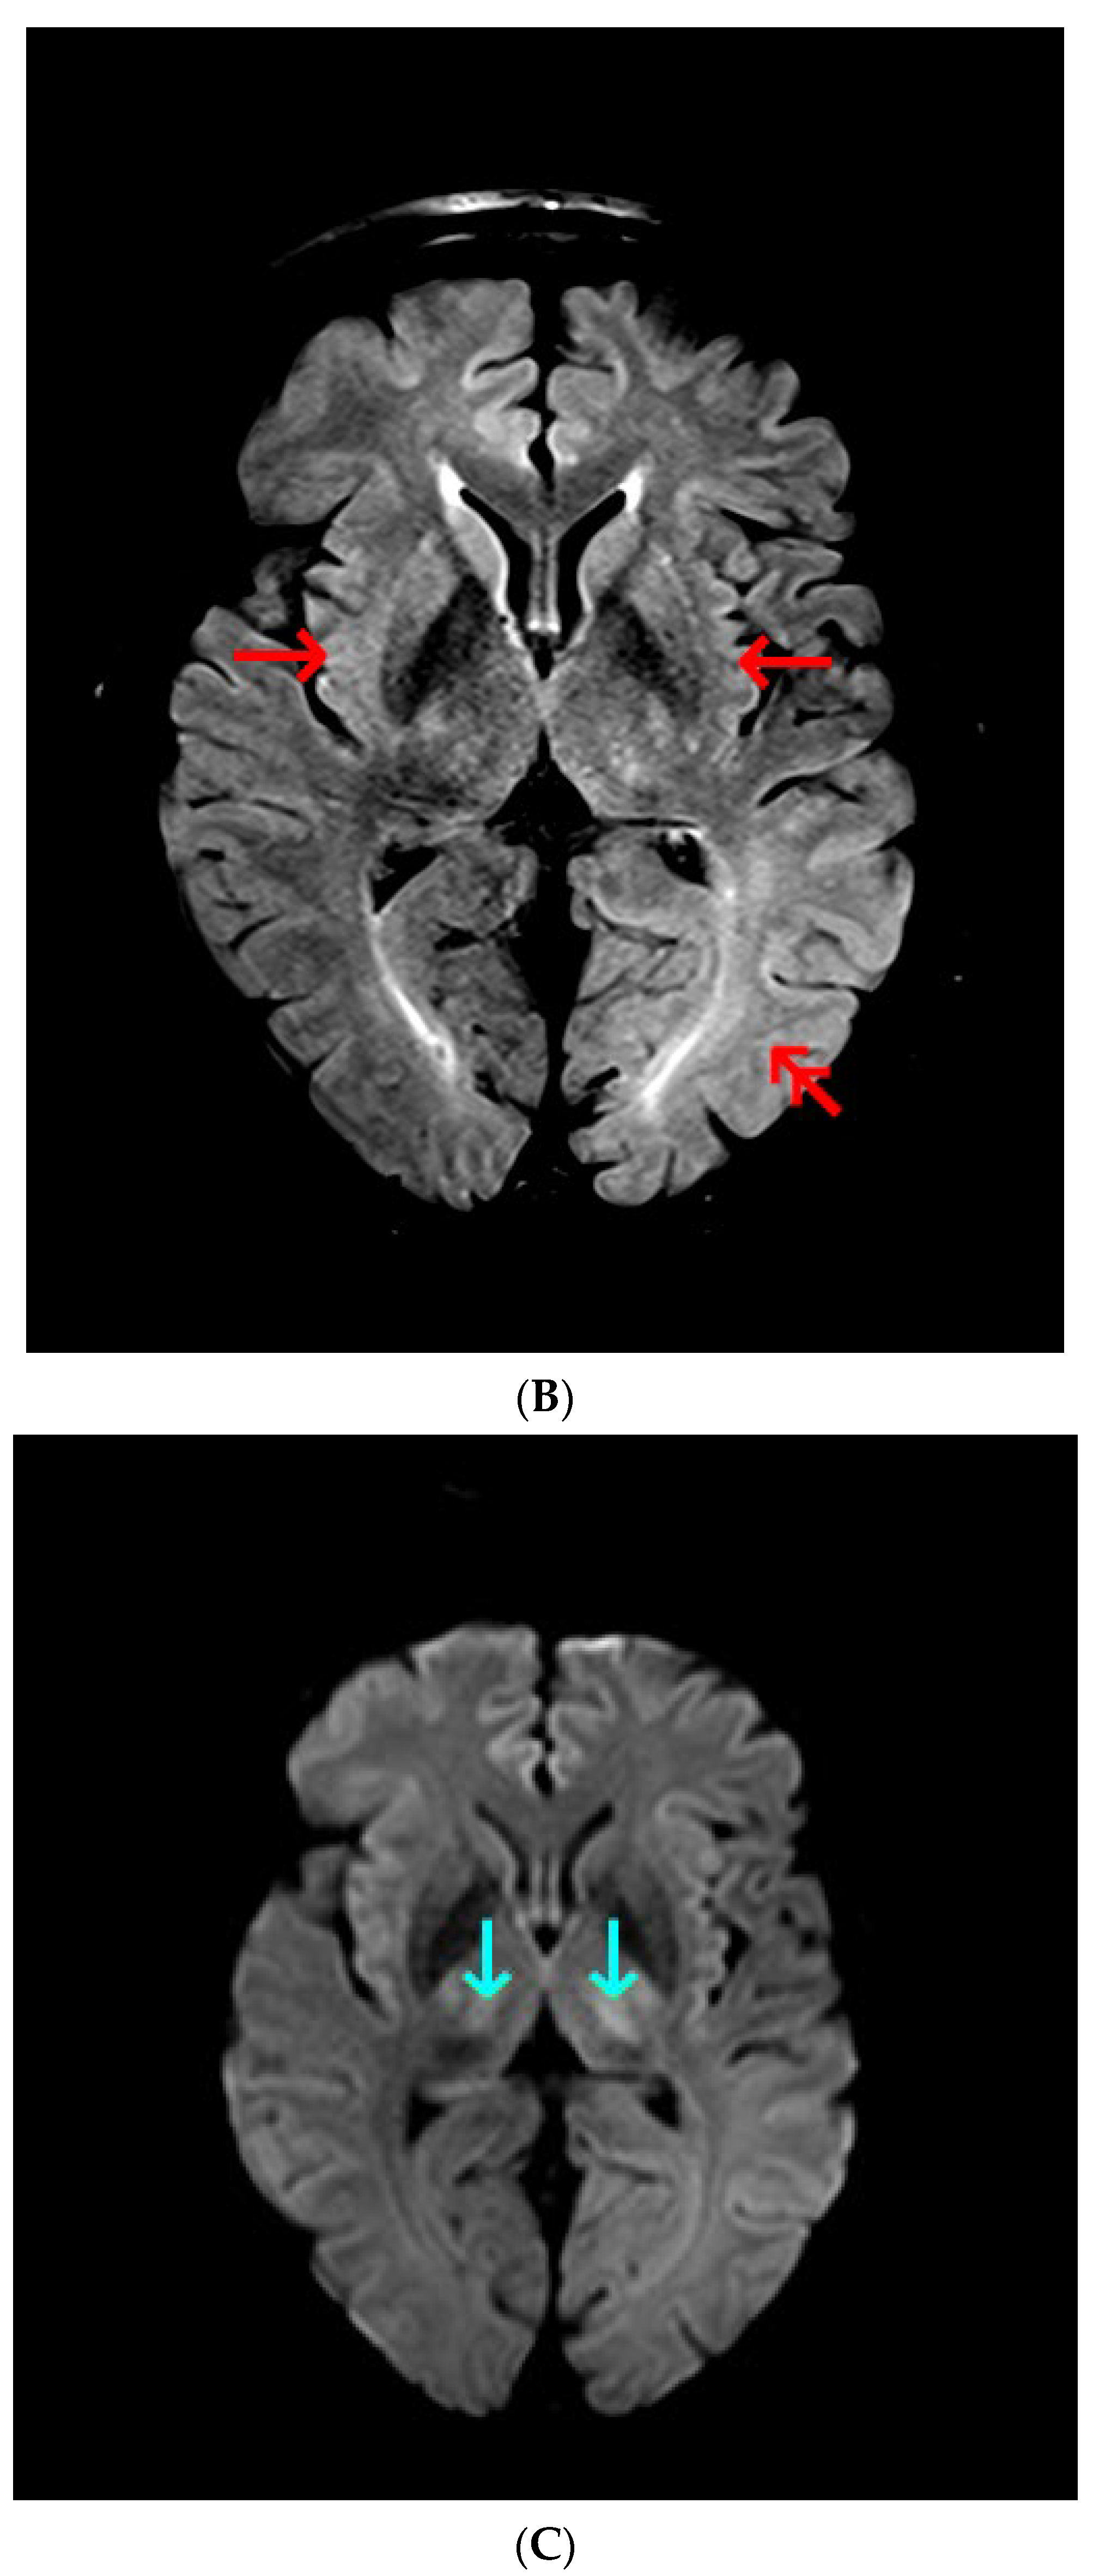

Common causes of decompensation of chronic liver disease include gastrointestinal (GI) bleeding, infection, high alcohol intake and hepatotoxic medications [1]. As the last three were unlikely, urgent esophagogastroduodenoscopy was ordered, however it showed non-bleeding esophageal varices and scarification following previous banding procedures in the middle and lower part of the esophagus. Gastrointestinal bleeding being the most likely cause of chronic liver decompensation was therefore excluded. In order to find the cause of impaired consciousness multimodal diagnostic assessment was initiated. Toxic screen showed absence of phenobarbital, carbamazepine, benzodiazepines, tricyclic antidepressants; valproic acid was present in the subtherapeutic concentration of 41 µg/mL (therapeutic range 50–100 µg/mL). On day 3 of ICU hospitalization angio-CT of the head was performed and also revealed no abnormalities. The EEG showed no signs of epileptiform activity, although generalized inhibition of basal activity was present. The direct chemiluminescence of the cerebrospinal fluid (CSF) performed on day 4 showed absence of IgG and IgM against B. burgdorferii, Herpes simplex virus, and cytomegalovirus. There was no DNA of Ebstein-Barr virus detected in the CSF sample. The onco- and anti-neuronal immunoglobulin panel performed with indirect immunofluorescence was negative: anty-Amp, anty-Cv2.1, anty-PNM2/Ta (Ma2/Ta), anty-Ri, anty-Yo, anty-Hu, anti-Rec, anti-SOX1, anti-titin. The anti-neuronal screen performed with indirect immunofluorescence was negative: anty-AMPA (GluR1/GluR2), anty-GABA B, anty-NMDA, anty-DPPX, anty-CASPR 2, anty-LGl 1). All initial microbiology cultures (blood, aspirate, urine, CSF) were negative. As part of diagnostic assessment the magnetic resonance imaging (MRI) examination of the head was performed on day 5. The image obtained by MRI is depicted in Figure 1A–D.

Figure 1.

(A) Magnetic resonance imaging of the head. T1 Spin Echo, axial. Green arrows point to hyper-intense globi pallidi; (B) Magnetic resonance imaging of the head. T2 Turbo Spin Echo Dark-fluid. Red single arrows point to the mild symmetric hyper-intensity in the insulas; double red arrow point to the pronounced hyper-intensity in the left occipital lobe; (C) Magnetic resonance imaging of the head. Diffusion Weighted Imaging b = 1000, axial. Cyan arrows point to the restricted water diffusion in both thalami; (D) Magnetic resonance imaging of the head. Apparent Diffusion Coefficient, b = 0, b = 1000, axial. Cyan arrows point to the restricted water diffusion in both thalami.

Taking into account clinical picture the differential diagnosis involved: chronic liver encephalopathy, acquired hepatocerebral degeneration (AHD), acute liver encephalopathy. Various nonspecific, not limited to vascular supply region, lesions of the brain, including rare appearance like T1 gray matter hyper-intensity, were consistent with hepatic encephalopathy. Because liver encephalopathy was a possible diagnosis, ammonia concentration was determined. The ammonia concentration determined with spectrophotometry reached 417 µg/dL, highly above the reference range (31–123 µg/dL). Ammonia was found to be an independent risk factor for hepatic encephalopathy and intracranial hypertension, the latter occurring in 55% of patients with ammonia concentrations >200 μmol/L (340.6 µg/dL) [2].